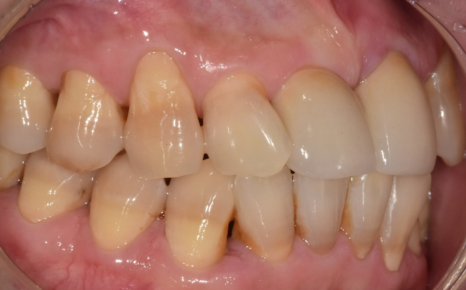

이 환자분이 저희 병원에 오시게 된 이유들은 다음과 같습니다.

230413

왼쪽 앞니가 아래로 더 내려앉는 느낌

찬 것만 먹어도 시린 증상

앞니 사이 틈이 점점 넓어지는 변화

시간이 지날수록 위의 증상이 심해져서 고민하고 계셨습니다.

입안을 확인했을 때,

해당 부위 잇몸 안쪽으로 치석이 보였습니다.

230413 잇몸 내려감으로 길어진 치아, 방치하면 안 되는 원인, 증상, 이유

정확한 상태 확인을 위해 엑스레이 촬영과 검사를 진행한 결과,

치석으로 인해 잇몸병이 진행되면서

잇몸뼈가 일부 녹아 있는 상태였습니다.

230413 / 230417